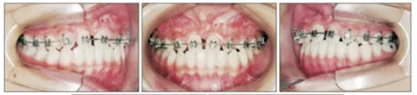

上頜前磨牙萌出后取出唇舌弓,上固定矯治器以排齊上頜牙列,該階段面弓暫時(shí)停止使用。

為最小化在青春后期上頜前傾,行骨支抗面弓(面弓聯(lián)合微鈦板[FM-MP])。在15歲1月時(shí)于雙側(cè)上頜骨顴突區(qū)植入兩枚微種植板,4周后加正畸力(500g/邊,與合平面呈30°向下,12-14時(shí)/天),持續(xù)3年5月。